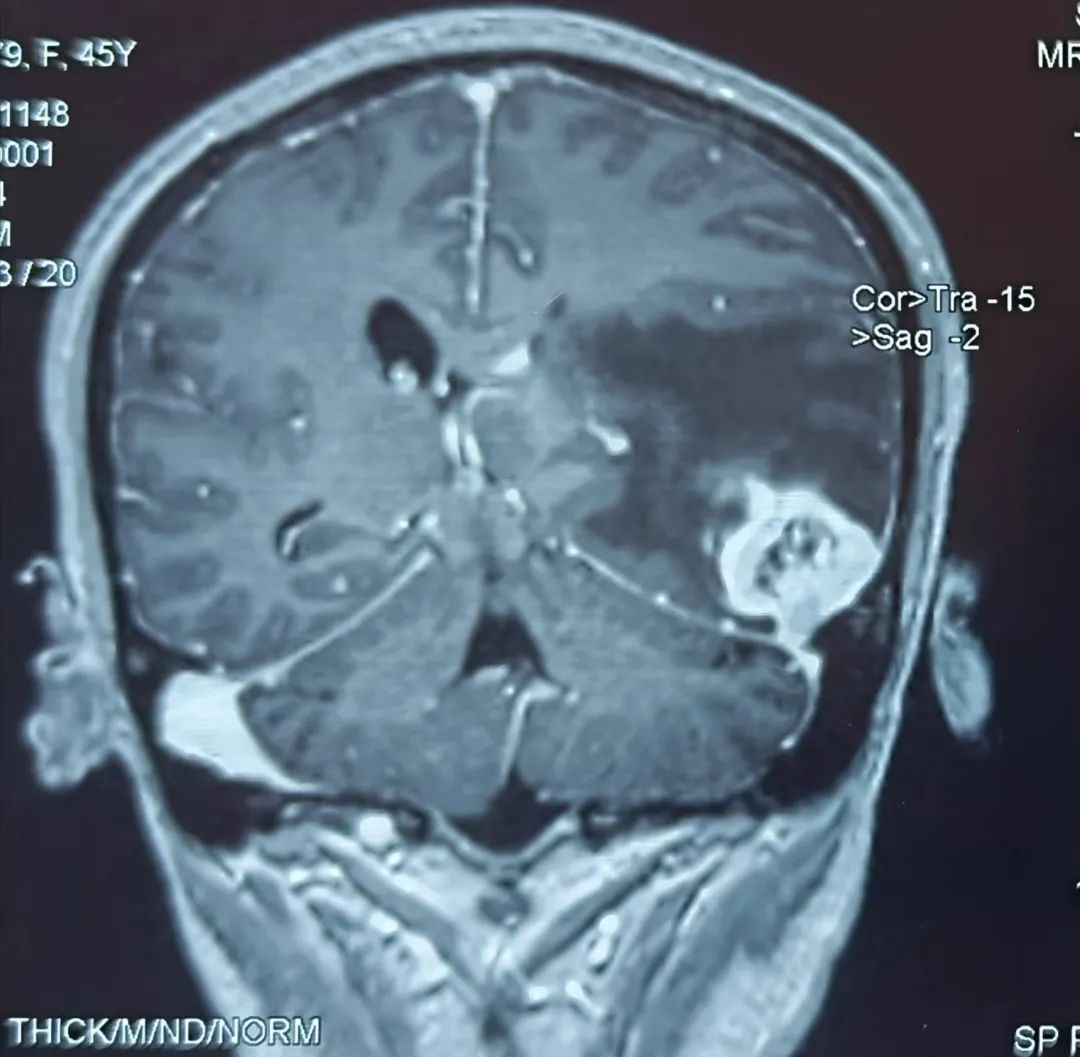

患者43岁,肾肿瘤术后一个半月开始出现头痛难忍,伴有恶心、呕吐、言语不流利,每天靠止痛药缓解头痛,到医院行头部核磁检查提示左颞叶占位,考虑脑转移瘤可能性大。为进一步诊治,在朋友的介绍推荐下,患者来到我院神经外科找到桑文渊主任。桑主任详细询问病史,仔细阅片后,初步诊断患者为脑转移瘤。

患者术前核磁影像